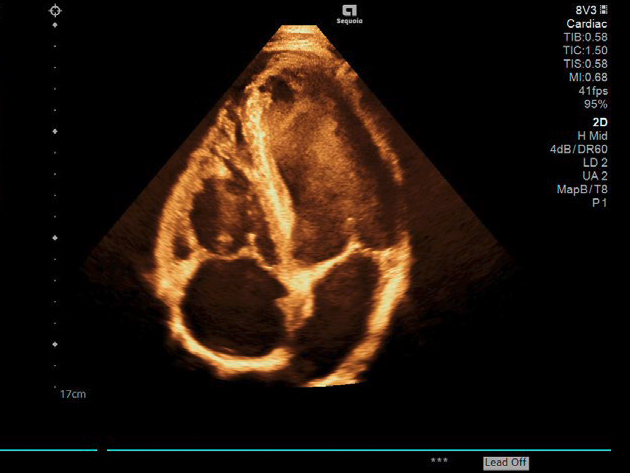

Απεικόνιση 2